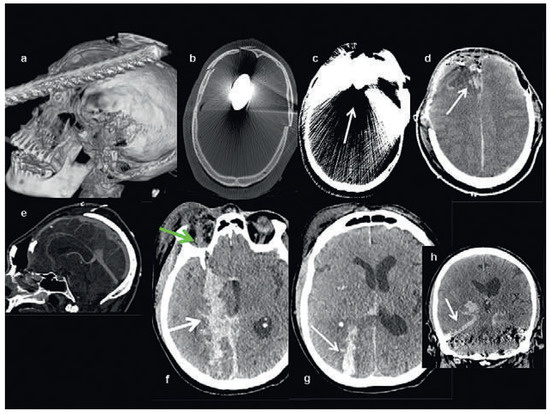

Head and brain trauma: general aspects and neuroimaging

by Johanna Maria Lieb, Christoph Stippich and Meritxell Garcia

Swiss Arch. Neurol. Psychiatry Psychother. 2015, 166(8), 279-292; https://doi.org/10.4414/sanp.2015.00374 - 1 Jan 2015

In this article the general clinical aspects, imaging indications and different injury mechanisms of traumatic brain injury (TBI) are reviewed. In addition, the different imaging modalities and strategies are presented, including more specific imaging features of the various injuries. Computed tomography (CT) is [...] Read more.

In this article the general clinical aspects, imaging indications and different injury mechanisms of traumatic brain injury (TBI) are reviewed. In addition, the different imaging modalities and strategies are presented, including more specific imaging features of the various injuries. Computed tomography (CT) is the imaging modality of choice in the acute phase owing to its wide availability and short scanning time, as well as to its high sensitivity for the detection of fractures and acute bleeding. Although magnetic resonance imaging (MRI) is superior to CT in many other aspects, it plays no role in the acute phase. MRI, however, has been proven to be useful and complementary to CT in the subacute and chronic stages as well as in the case of inconclusive results on initial CT. Especially the use of standard sequences like fluid attenuated inversion recovery (FLAIR), diffusion and susceptibility weighted imaging (DWI and SWI) have been shown to increase the diagnostic potency in diffuse axonal injury, in mild brain trauma and also in more chronic stages of TBI. The use of more advanced MRI techniques such as diffusion tensor imaging (DTI), magnetic resonance spectroscopy (MRS), functional MRI (fMRI) and magnetic transfer imaging (MTI) can further complete the diagnostic evaluation and give insights into different pathophysiological processes in TBI. Full article